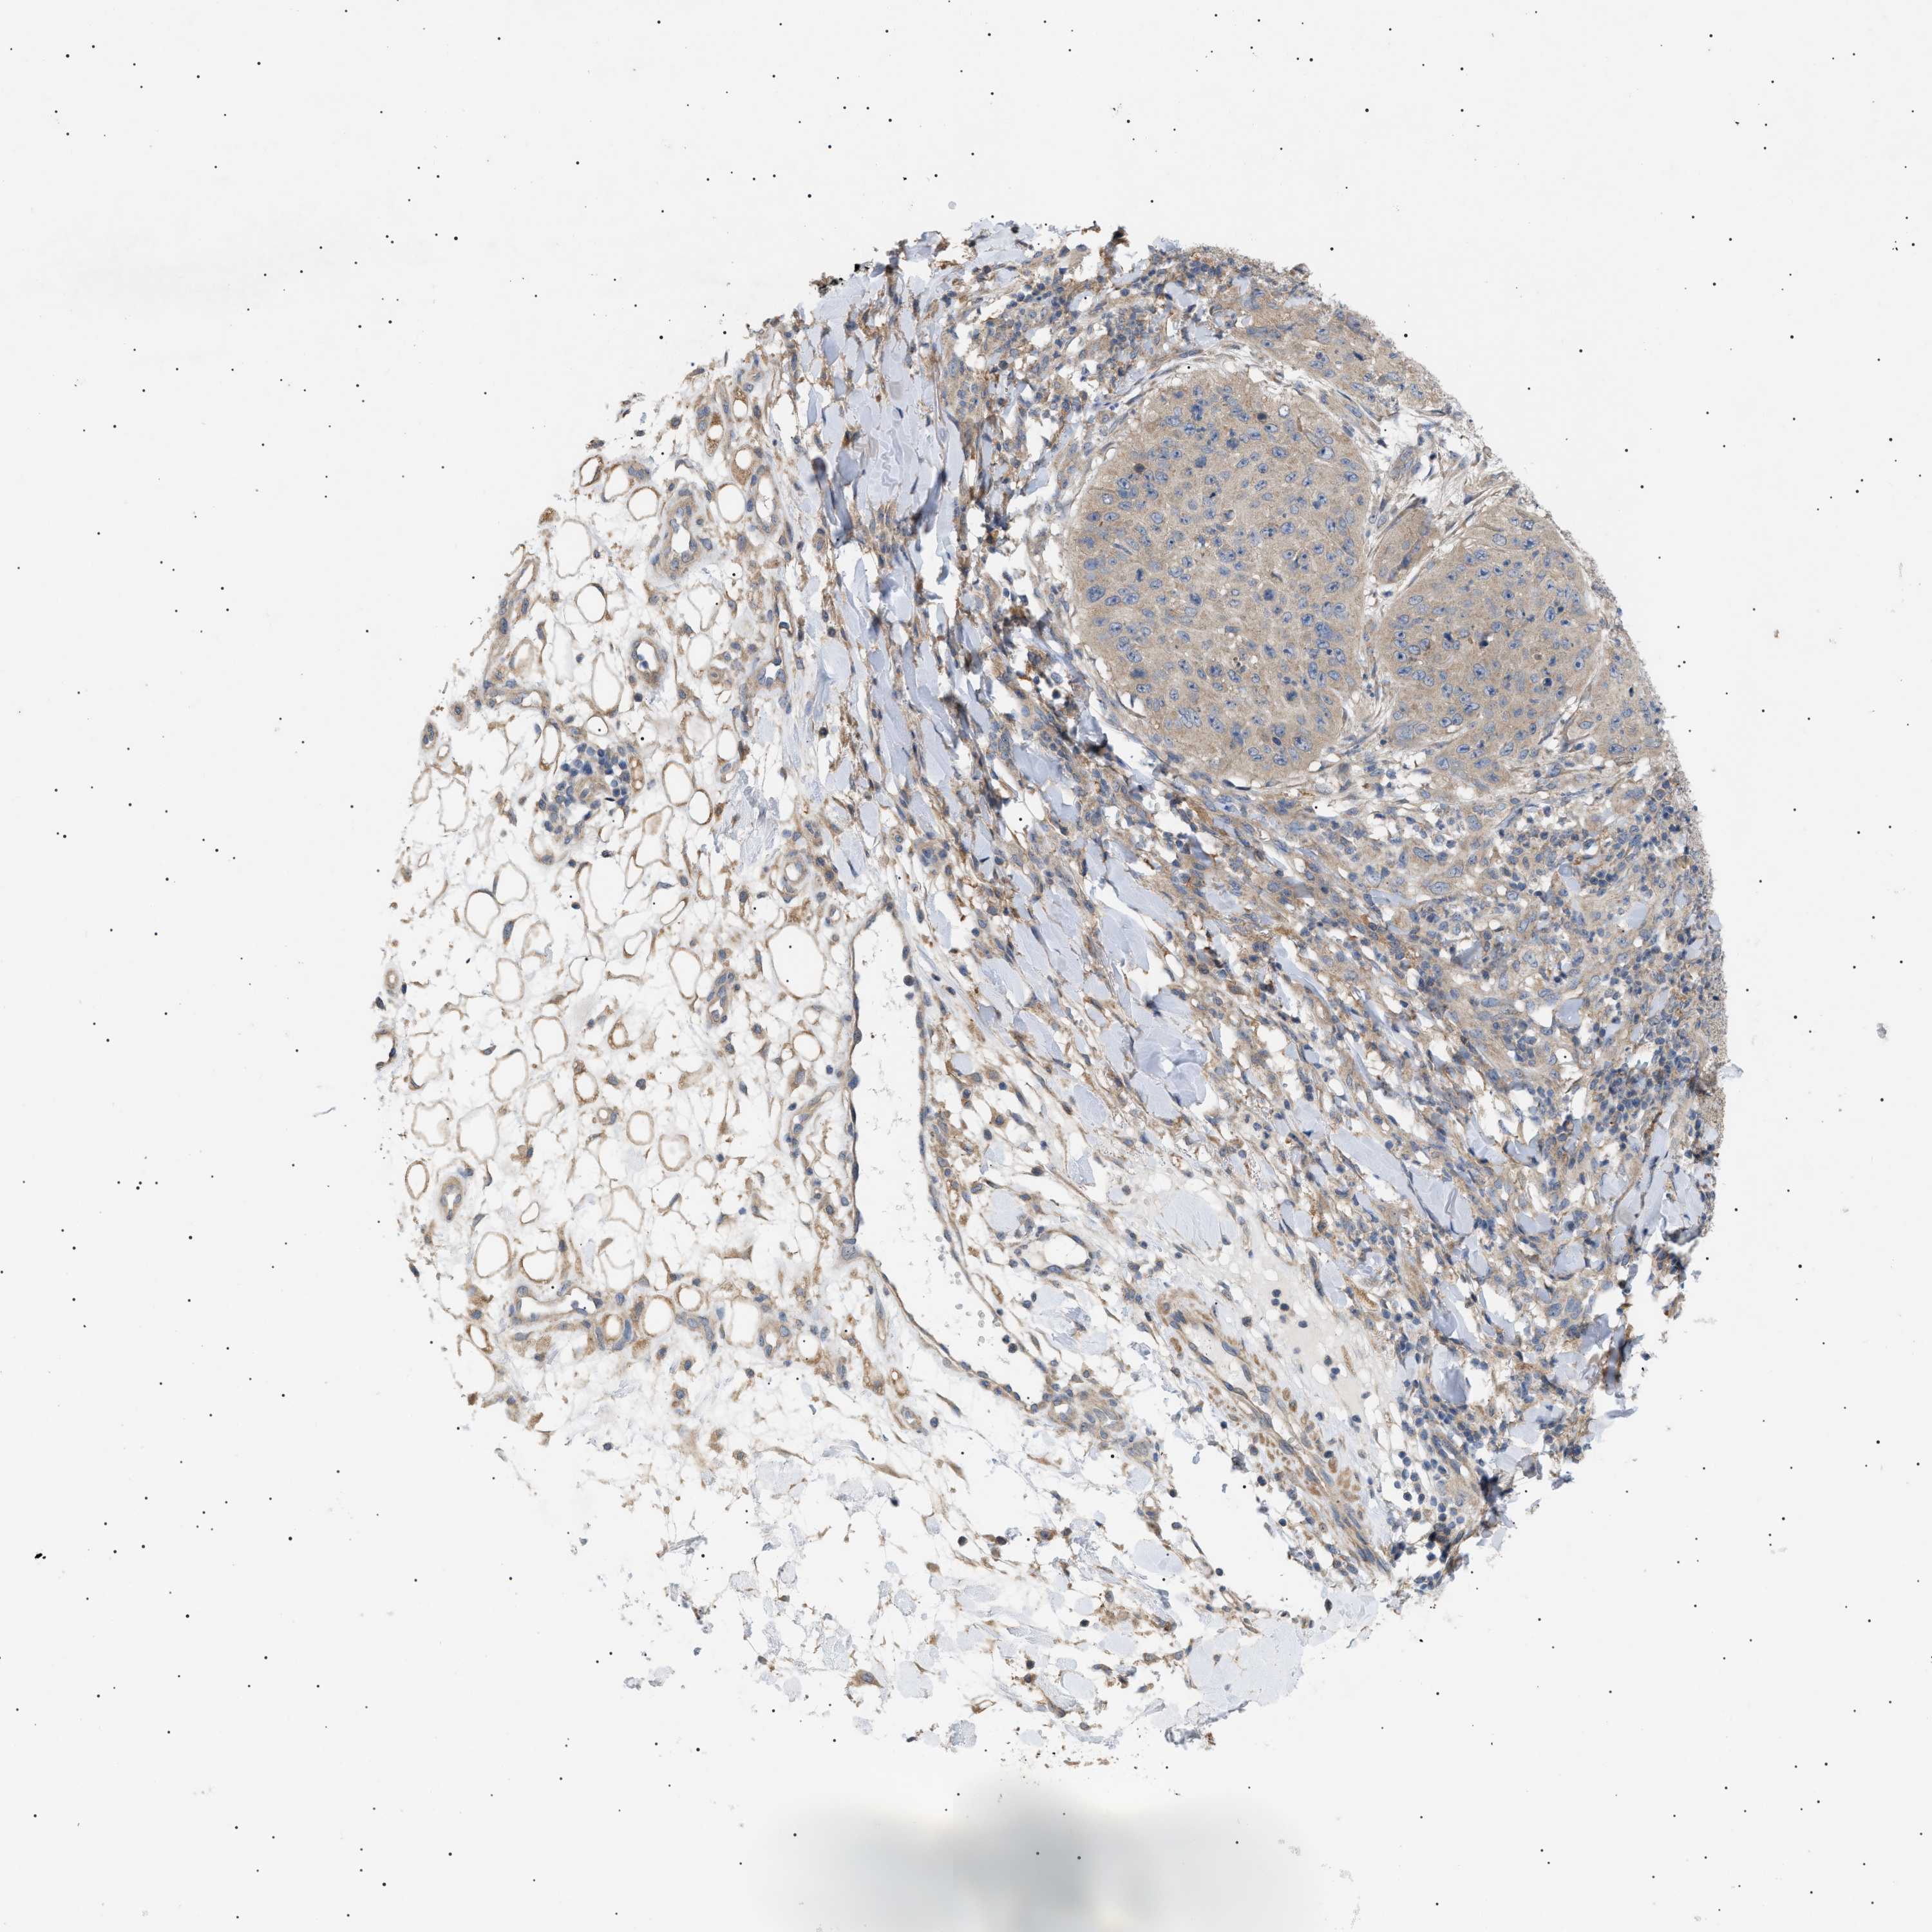

Basal cell and squamous cell cancer

SKIN CANCER - Protein expressioni

A mouse-over function shows sample information and annotation data. Click on an image to view it in a full screen mode. Samples can be filtered based on level of antibody staining by selecting one or several of the following categories: high, medium, low and not detected. The assay and annotation is described here.

Note that samples used for immunohistochemistry by the Human Protein Atlas do not correspond to samples in the TCGA dataset.

Antibody stainingi

Antibody staining in the annotated cell types in the current human tissue is reported as not detected, low, medium, or high, based on conventional immunohistochemistry profiling in selected tissues. This score is based on the combination of the staining intensity and fraction of stained cells.

Each image is clickable and will lead to virtual microscopy that enables deeper exploration of all samples and also displays staining intensity scores, fraction scores and subcellular localization as well as patient and tissue information for each sample.

Antibody CAB016944

Staining

High

Medium

Low

Not detected

Intensity

Strong

Moderate

Weak

Negative

Quantity

>75%

75%-25%

<25%

None

Location

Nuclear

Cytoplasmic/membranous

Cytoplasmic/membranous,nuclear

Squamous cell carcinoma in situ, NOS

Squamous cell carcinoma, NOS

Squamous cell carcinoma, metastatic, NOS

Basal cell carcinoma

Adnexal tumor, benign